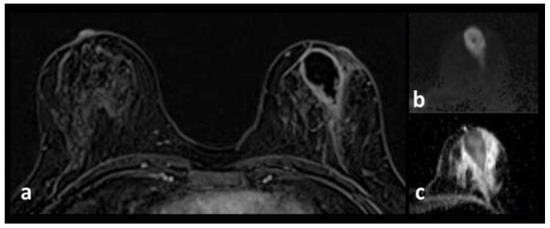

Intramammary Lymph Node